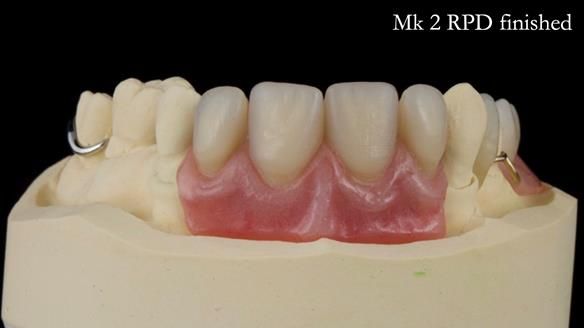

Jean’s Class I Mod III RPD: Learning from My Mistakes – From a Fractured Mk1 to a Stronger Mk2 (4 Years On)

In this edition, I present the removable partial denture treatment for Jean, an 80-year-old woman with a sore mouth caused by a soft tissue-supported 'gum stripper' acrylic denture and a clenching habit. Below, I outline the step-by-step process of her treatment. It wasn't straightforward; I had to remake the denture after it fractured to achieve a satisfactory result. Each patient is unique, and sometimes a new RPD serves as a prototype. Occasionally, I need to make adjustments, learn from any mistakes, and refine the design to get it right.

The treatment has been a success over the past 4 years.